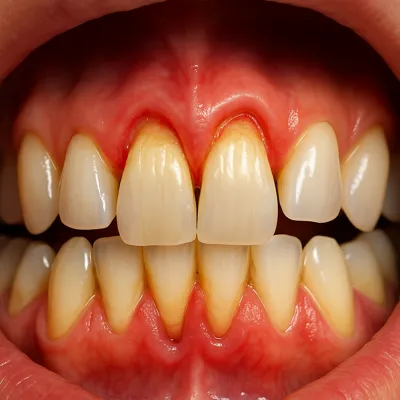

دندان عقل در انتهای دهان قرار دارد و بهخوبی تمیز نمیشود؛ همین موضوع احتمال گیر غذایی، التهاب لثه و عفونتهای مکرر را بالا میبرد. عفونتهای تکرارشونده میتوانند به دردهای مداوم و حتی دردهای مزمن فک منجر شوند.

با گذشت زمان، فشار دندان عقل به دندانهای کناری میتواند باعث آسیب به دندان مجاور، پوسیدگی بیندندانی یا تحلیل استخوان موضعی شود؛ مشکلاتی که درمان آنها ساده نیست.

درد ضرباندار، بوی بد دهان، تورم لثه یا ترشح میتواند نشاندهنده التهاب یا عفونت باشد. در چنین شرایطی ممکن است ابتدا کنترل عفونت و سپس جراحی انجام شود تا هم بیحسی بهتر اثر کند و هم تجربه درمان آرامتر شود.